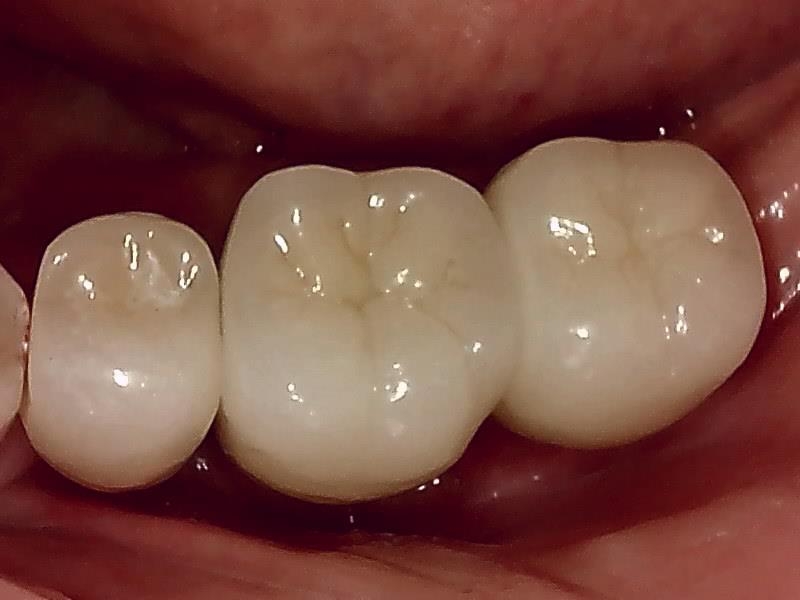

インプラントの上部構造 (左下)

(ジルコニアセラミッククラウン)

術後、とても経過良好です。